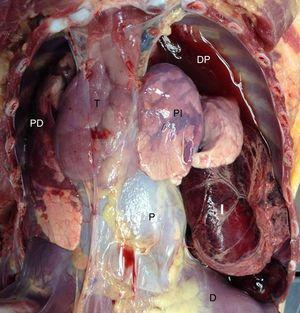

Se presenta el caso de un niño de 13 meses sin antecedentes médicos, que llega al centro de salud en situación de parada cardiorrespiratoria y fallece tras maniobras de RCP avanzadas. Había sido visitado en el mismo centro 5h antes por cuadro de dolor abdominal con 2 episodios de vómito alimenticio y febrícula (37,4°C). Desarrollo estaturo-ponderal adecuado, externamente no se hallaron lesiones ni otros hallazgos relevantes. El examen interno reveló en hemitórax izquierdo un derrame pleural serohemático y la presencia de una amplia porción intestinal de aspecto necrótico-hemorrágico con desplazamiento de estructuras mediastínicas (fig. 1). Se identificó orificio localizado en la porción posterolateral izquierda del diafragma, a través del cual se había producido la herniación (fig. 2). No se hallaron otras malformaciones congénitas. El estudio toxicológico fue negativo y el estudio histopatológico informó también de un cierto grado de colapso pulmonar izquierdo y signos de aspiración alimentaria terminal difusa. La presentación tardía (después del primer año) de la HDC como causa de muerte súbita es excepcional.